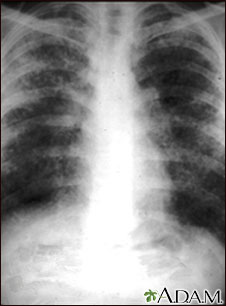

A chest x-ray is an x-ray of the chest, lungs, heart, large arteries, ribs, and diaphragm.

You stand in front of the x-ray machine. You will be told to take a breath in and hold it when the x-ray is taken.

Two images are usually taken. You will first need to stand facing the machine, and then sideways.